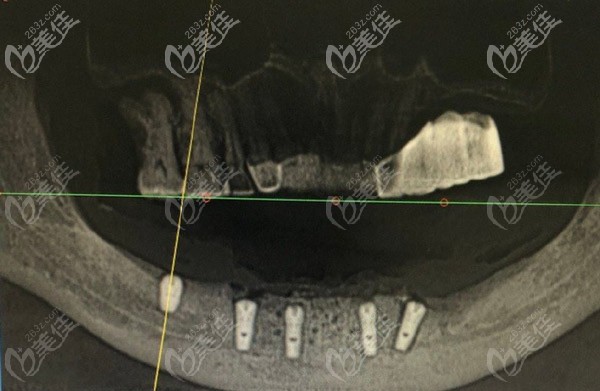

VIIV缺骨種植技術(shù)的原理:

突破了傳統(tǒng)種植牙對(duì)牙槽骨條件的限制,顧客不需要植骨,不用在等長(zhǎng)達(dá)一年的時(shí)間,就可以種牙。

采用的是哪里有骨哪里種,通過(guò)不同角度種植的方式,只需要4-6顆種植體就能恢復(fù)半口牙,避免多次手術(shù)的創(chuàng)傷。m.xqnp.cn

即刻種植:4-6顆植體恢復(fù)半口牙,當(dāng)天種牙當(dāng)天吃美食。

缺骨種牙:無(wú)需植骨,避免骨粉、骨膜費(fèi)用及植骨費(fèi)用。

適應(yīng)癥廣:牙槽骨萎縮、骨質(zhì)疏松、無(wú)牙頜也能輕松種牙。